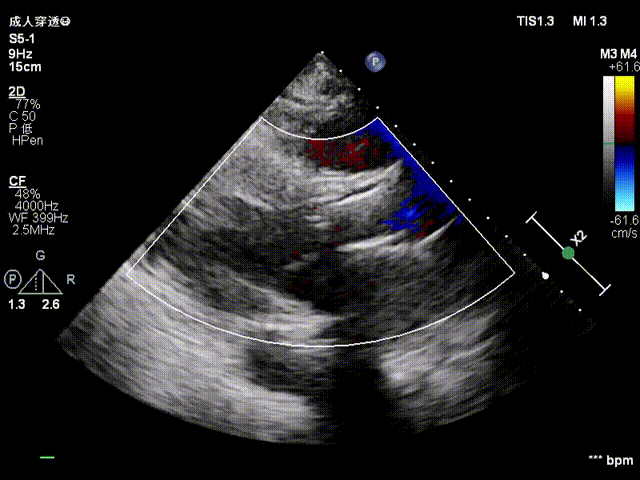

超声评估

植入后超声评估:植入位置良好,无明显瓣周漏

超声多切面评估,血流动力学改善明显,无瓣周漏